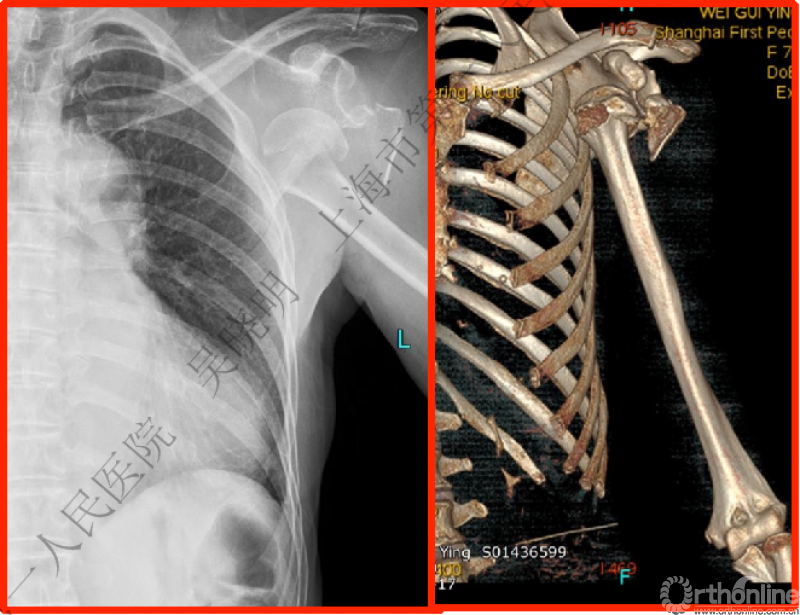

下图考虑为孤立性的大结节骨折?

看完片子,你会发现高质量的平片甚至3D CT也难以发现

X线看不清骨折线,三维CT也看不清